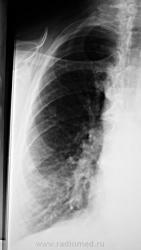

По рентгенографии органов грудной клетки в легких не менее 4 образований... Поскольку живем не в юго-восточной Азии с паразитами, предполагаем в первую очередь метастазы.

По УЗИ - в малом тазу "гуля" 25 см в диаметре

Из истории заболевания - оперирована по "женски" чуть больше 1 года назад, получала лучевую терапию....(гинекологи в направлении пишут рак влагалища..